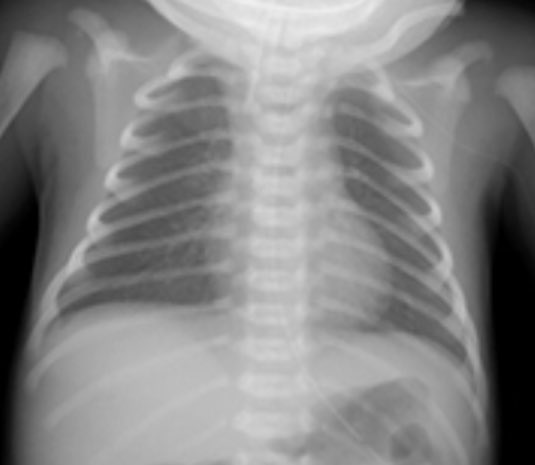

新生児ってこんな感じ。 肩とか肋骨とか違うでしょ。 親を心配させないでほしい。 twitter.com/nobusinsan/sta…